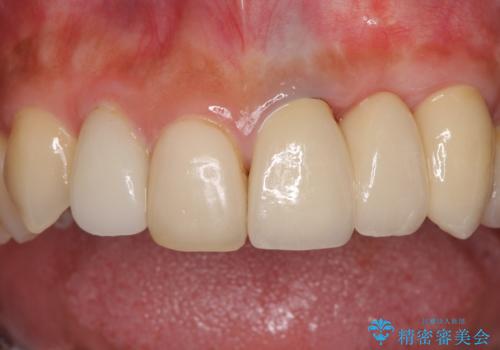

歯肉移植を用いた前歯のオールセラミックブリッジ

- 前歯が折れてしまい、ブリッジによる補綴治療を希望して来院された患者様です。

折れている前歯は抜歯をし、痩せてしまう歯肉は移植術により増大させることで審美面を回復した後、オールセラミックブリッジにて補綴することとしました。

インプラントかブリッジか悩むところでしたが、既に治療されている前歯のクラウン周りの変色が気になっていたため、ブリッジにより色調を合わせたオールセラミックを装着することを選択しました。

歯肉ラインや歯の形態、色調を整えることができ、患者様には大変満足していただきました。